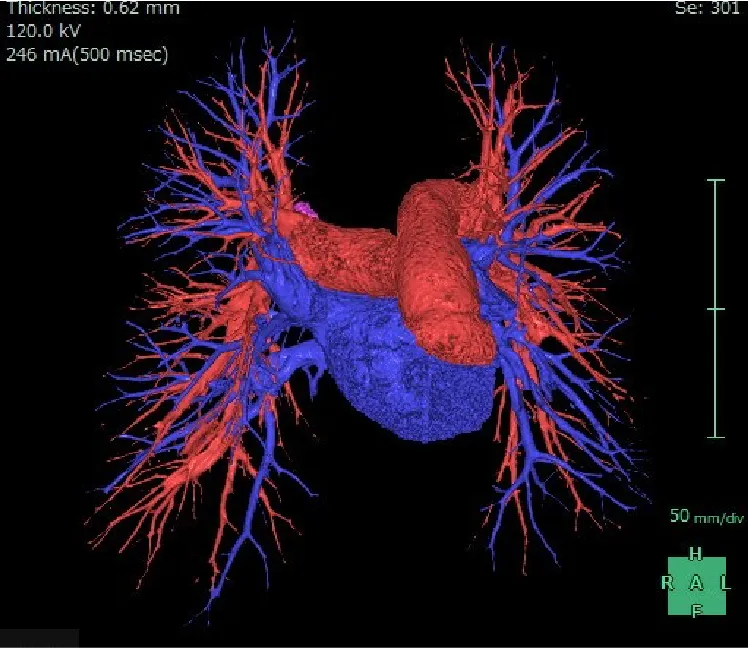

CT(コンピュータ断層装置)

CTは Computed Tomography(コンピュータ断層撮影) の略で、X線を使って体の断面を撮影する装置です。体の内部構造を詳しく画像化できるため、さまざまな病気の発見に役立ちます。近年の技術進歩により、0.5mm間隔で断層画像を撮影できるため、ごく小さな病変も見つけることが可能になりました。また、得られた断面画像を重ね合わせることで、立体的な3D画像を作成することもできます。さらに、必要に応じて 造影剤 を使用すると、腫瘍などの病変部位がより明瞭に写り、周囲の血管の走行や栄養血管の状態を詳しく把握することができます。ただし、造影剤には副作用の可能性があり、また腎機能が著しく低下している場合には使用できないことがあります。造影剤を使うかどうかは、検査内容に応じて医師が判断します。